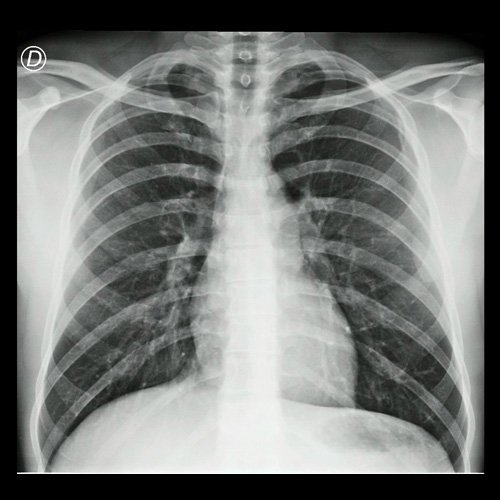

• Radiografía de tórax frente (Día 3): centrada, índice cardiotorácico conservado , senos costofrénicos libres. Sin consolidaciones pleuroparenquimatosas.

Radiografía de tórax frente y perfil  Día 3